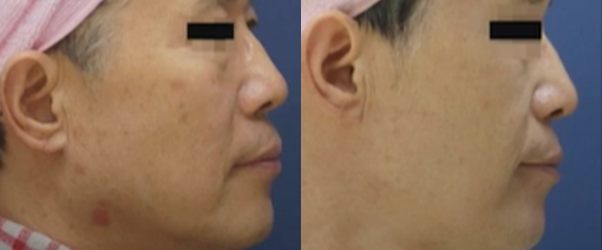

ลดความหย่อนคล้อย

ลดความหย่อนคล้อย